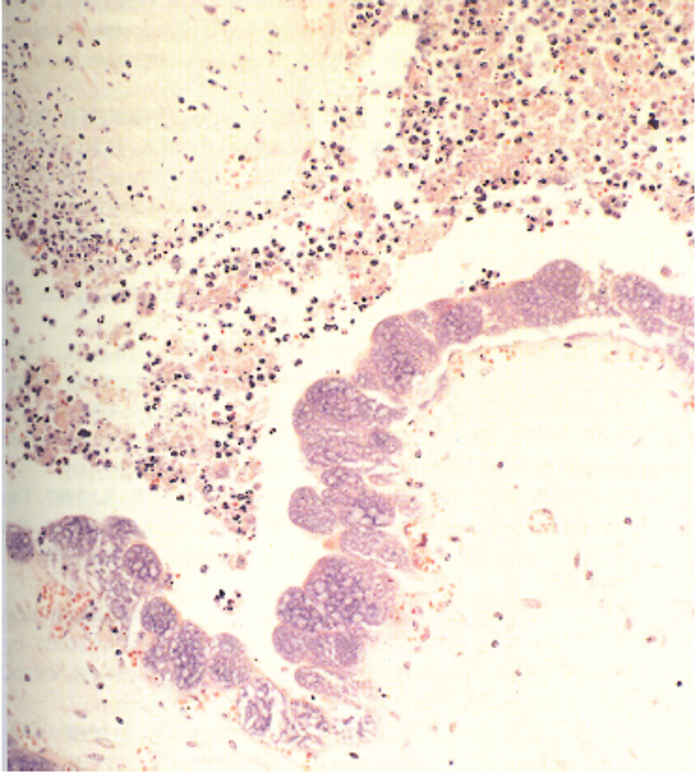

Few lesions have been reported in domesticated animals. Varying degrees of inflammation and necrosis of the cotyledons65, 76 occur in sheep and goats that have aborted as a result of C. burnetii infection. The placental lesions are most conspicuous in the intercotyledonary zone and are covered by abundant, inspissated exudate. The foetal membranes beneath the exudate are thickened, leathery and diffusely red to brownish. Multifocal areas of calcification, which tend to become confluent, also occur. The cotyledonary villi are necrotic, a prominent neutrophil infiltration occurs, and many C. burnetii are present in the trophoblast cells of the allantochorion (Figure 43.4). No gross lesions have been recorded in the foetus.61 In Coxiella- positive placentas from cattle that have aborted, placentitis occurs with the chorionic stroma infiltrated with mononuclear cells, necrosis of the chorionic trophoblast and focal exudation of fibrin and neutrophils.15 The placentitis in cattle is usually milder than that in sheep and fewer C. burnetii can be demonstrated immunocytochemically. 89

Staining with Giménez32 or the modified Ziehl-Neelsen stain (Figure 43.5)15 may be used to demonstrate organisms in impression smears made from affected cotyledons and chorion of placentas from animals that have aborted. Gram staining is unreliable, with C. burnetii appearing Gram positive under some conditions.33 Differentiating C. burnetii from other agents of abortion, for example Chlamydophila and Brucella, is often difficult in stained smears and immunofluorescence with mono- or polyclonal antibodies is recommended. This technique may be used on fresh and paraffin-embedded tissues. Organisms may also be detected with immunoperoxidase assays19, 89 and capture enzyme-linked immunosorbent assay (ELISA) or ELIFA84 but these techniques require fresh tissue. Care should be taken in interpreting results as C. burnetii may also be found in placentas of healthy sheep and goats.95